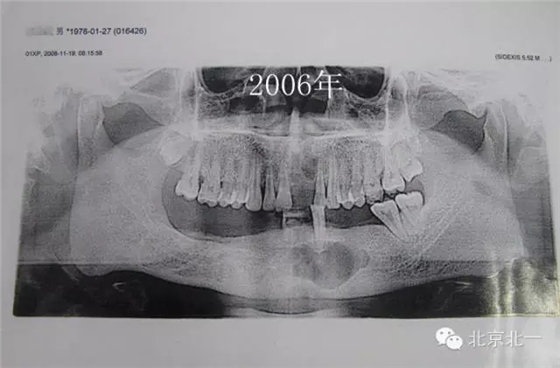

患者男,33歲,左下頜囊腫復(fù)發(fā)兩次就診。

圖2、手術(shù)后第一次復(fù)發(fā)